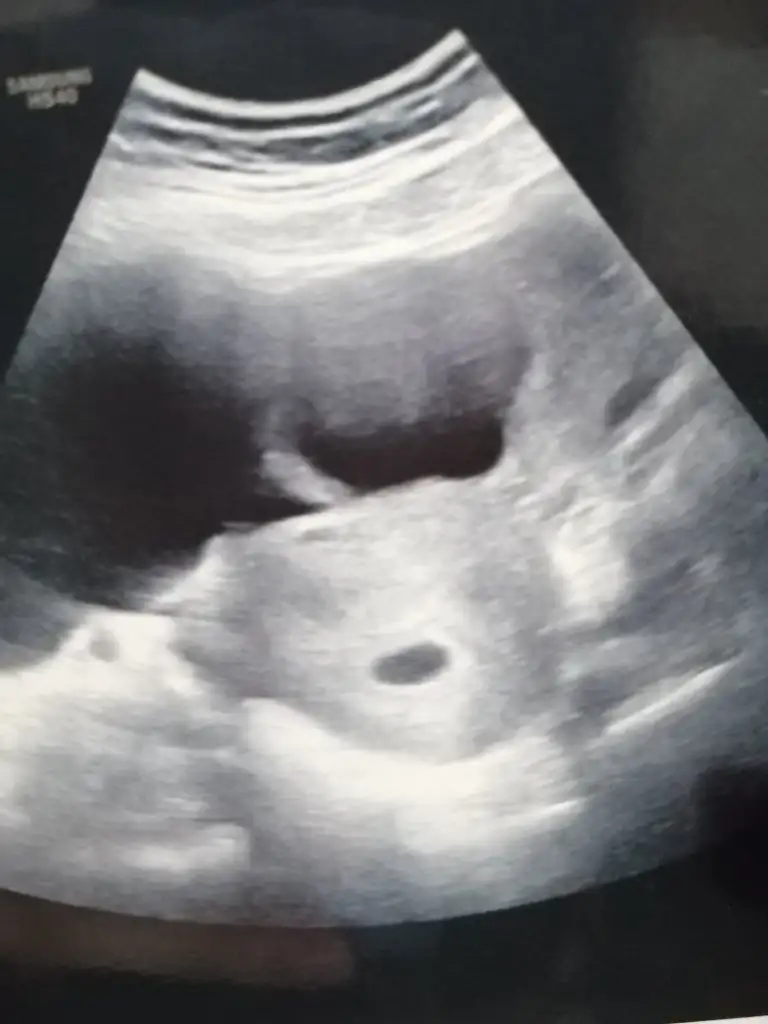

Maşallah canım hayırlı olsun hiç de geç kalmamışsın keseyi de gayet güzel görmüşsün daha ne olsun. Bol bol dinlen bu dönemde kendini hiç yorma bu sefer her şey yolunda gidecek inan buna psikolojin çok önemliSelamlar bugün 5+5 oldum.

Keseyi gördük. Şükürler olsun.

Her zaman aynı şey olmaz kiSelamlar bugün 5+5 oldum.

Bir dahaki randevum 10 mayısda